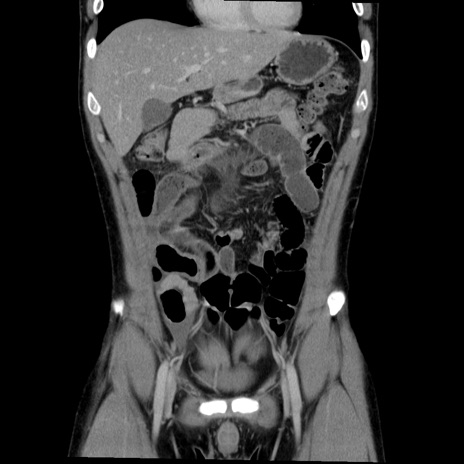

症例36(冠状断像)

【症例】20歳代 男性

【主訴】心窩部痛

【現病歴】今朝より上腹部痛あり。一旦軽快していたが再度出現したため救急要請。昨日夕に白身の魚を含む刺身を食べた。

【身体所見】BP 136/89mmHg、HR 74/min、BT 37.0℃、腹部:膨満、軟、心窩部に圧痛あり。反跳痛なし、筋性防御なし、腸雑音やや亢進あり。

【データ】WBC 17700、CRP 0.48